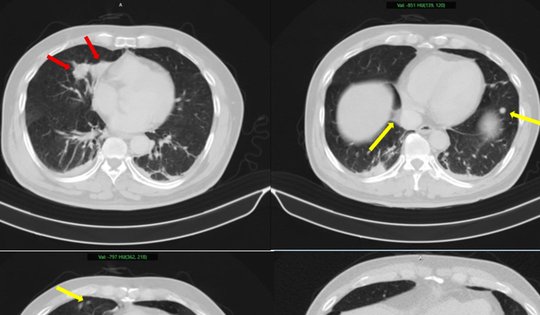

Bác sĩ chỉ ra 5 dấu hiệu cảnh báo ung thư phổi dễ bị phớt lờ

25/01/2026 11:00

Ung thư phổi có thể phát hiện sớm qua 5 dấu hiệu: ho kéo dài, khó thở, đau ngực hoặc lưng, khàn tiếng và sụt cân đột ngột.